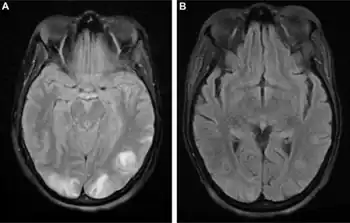

Posterior reversible encephalopathy syndrome visible on magnetic resonance imaging as multiple cortico-subcortical areas of T2-weighted hyperintense (white) signal involving the occipital and parietal lobes bilaterally and pons.

The diagnosis is typically made with magnetic resonance imaging of the brain. The findings most characteristic for PRES are symmetrical hyperintensities on T2-weighed imaging in the parietal and occipital lobes; this pattern is present in more than half of all cases.[1][2] FLAIR sequences can be better at showing these abnormalities.[3] Some specific other rare patterns have been described: the superior frontal sulcus (SFS) watershed pattern, a watershed pattern involving the entire hemisphere (holohemispheric), and a central pattern with vasogenic oedema in the deep white matter, basal ganglia, thalami, brainstem and pons.[1][2] These distinct patterns do not generally correlate with the nature of the symptoms or their severity, although severe edema may suggest a poorer prognosis.[1] If the appearances are not typical, other causes for the symptoms and the imaging abnormalities need to considered before PRES can be diagnosed conclusively.[3] In many cases there is evidence of constriction of the blood vessels (if angiography is performed), suggesting a possible overlap with reversible cerebral vasoconstriction syndrome (RCVS). Diffusion MRI may be used to identify areas of cytotoxic edema caused by poor blood flow (ischemia) but it is not clear if this prognostically relevant.[1][3] Abnormal apparent diffusion coefficient is seen in about 20% of cases.[3]